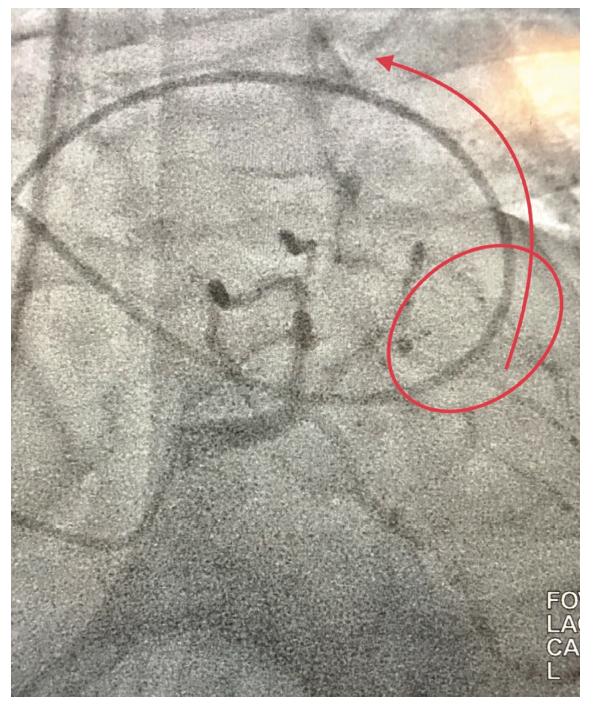

Although encountering an aberrant right subclavian during cardiac catheterization is quite infrequent, operators still do encounter it. For the most part, this congenital anomaly is unknown prior to the cath and is typically identified when a right radial approach is utilized. Upon entering the aorta, catheters frequently go into the descending aorta (due to the orientation and location of the junction of the right subclavian and aorta), which may be misconstrued as severe tortuosity.

With “standard” right subclavian tortuosity, the catheter crosses the right to left side of the trachea and has a rounded out shape (Figure 2B). Catheters also move inferiorly for a few centimeters before moving back right towards the trachea again, prior to reaching the sinotubular junction. In contrast, with an aberrancy, the catheter crosses the trachea and travels significantly left past the trachea and abruptly turns back to the right, towards the transverse and ascending aorta that is delineated quite well with an left anterior oblique (LAO)/caudal view. The catheter may also follow a superior trajectory before reaching and/or cannulating the coronary ostia (Figure 3).

We encountered five aberrant subclavians over a several-year period. Three were unknown prior to catheterization. One was known prior from a CT angiogram where we used a left radial approach (Figure 4A). One was done femorally; the anomaly was only identified when the catheter took an unusual course several times. Aortic root angiography was subsequently done and the aberrancy was identified (Figure 4B). Three were done from the right radial approach. Two were confirmed with angiography and one was later confirmed with a CT angiogram that had been done previously; however, this report was not available prior to the cath.